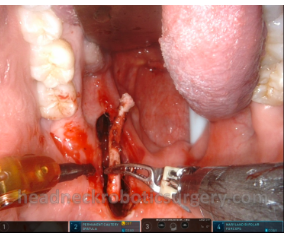

Surgical management of oropharyngeal cancer (both in the pharyngeal tonsil and in the base of the tongue) in the main indications for TORS. Learn more.

TORS approach to the parapharyngeal space is a minimal access surgical technique for diseases in this complex anatomical area. Learn more.

TORS eases the transoral approach for removing the elongated styloid process causing Eagle syndrome. Learn more.